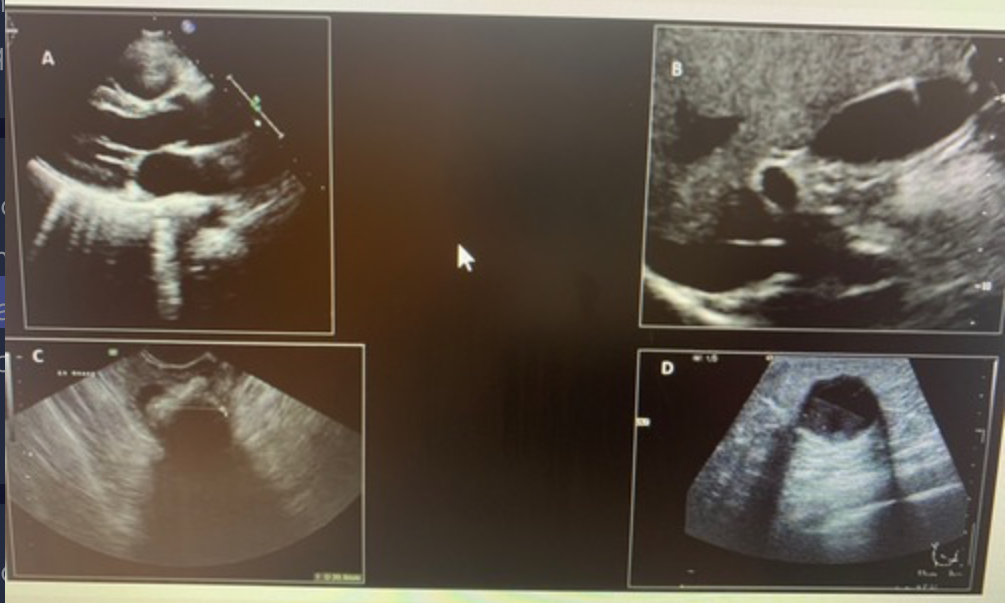

Which image demonstrates refractive shadowing?Use your mouse to position the cursor over the image and click to set your answer.

a. top left

b. top right

c. bottom left

d. bottom right

bottom right

Which image demonstrates posterior enhancement? Use your mouse to position the cursor over the image and click to set your answer.

top right